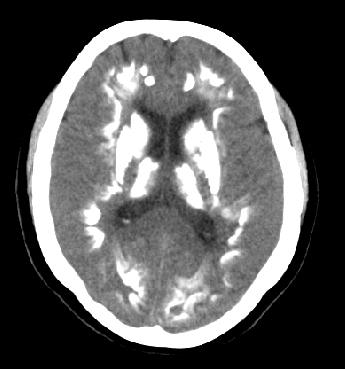

女性 38岁 病人脚弓反张 8岁以后不能行走 今年查pth11.9ng/ml(正常28ng/ml)

这么弥漫的钙化还第一次见。

考虑甲状旁腺功能减退症,该病是因甲状旁腺激素分泌减少或功能障碍所引起的少见病。其特点是低血钙,高血磷,且血pth极低。因低钙常可引起神经精神激惹症状,包括手指,趾,口角麻木,严重时可出现肌肉痉挛,喉哮鸣和惊厥,甚至癫痫样发作,有的可出现抑郁症及精神失常。长期的高磷血症可引起脑内结构对称性多发性钙化,特别是小脑和基底节的钙化可致锥体外系症状,而钙化的ct表现为类似于脑出血的密度增高影。

鉴别诊断:fahr 病,又称特发性家族性脑血管亚铁钙沉着症,是一种少见病,男女发病无显著差异,多为散发。临床表现为阵发性意识不清,首发症状开始于14~51 岁不等,以后呈阵发性发作,表现为突然神志丧失、跌倒、四肢抽搐约,发作后常表现为意识淡漠,性格改变,血清钙在正常范围。ct表现尾状核头呈倒“八”字形或片状钙化,在大脑半卵圆中心皮、髓质交界处多为点、小片状钙化,丘脑多呈对称小点、小条状钙化,小脑齿状核呈括弧形或不对称性小片状钙化。

原发性甲状旁腺功能减退症和fahr病都有神志上的改变等症状,且头颅ct检查均可见颅内出现钙化。但fahr病无pth低下,ct表现钙化影在大脑半卵圆中心皮髓质交界处、丘脑、小脑齿状核等处。 而甲状旁腺功能减退症pth极低,ct虽可见钙化影,但部位在小脑和基底节等处。